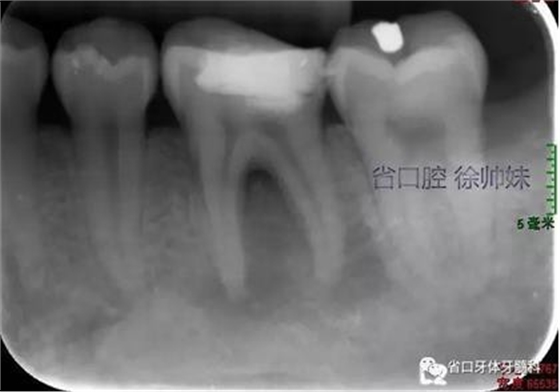

現(xiàn)病史:6個月前左下后牙區(qū)牙齦腫脹,反復(fù)溢膿,無明顯其他不適。4月前于我院牙體牙髓科(圖1)就診,診斷為“36牙周牙髓聯(lián)合病變”,建議試行36根管治療+牙周治療保留患牙,患者當(dāng)時未行治療。現(xiàn)再次來我院牙體牙髓科要求進一步診治。

圖1 術(shù)前4月的根尖片